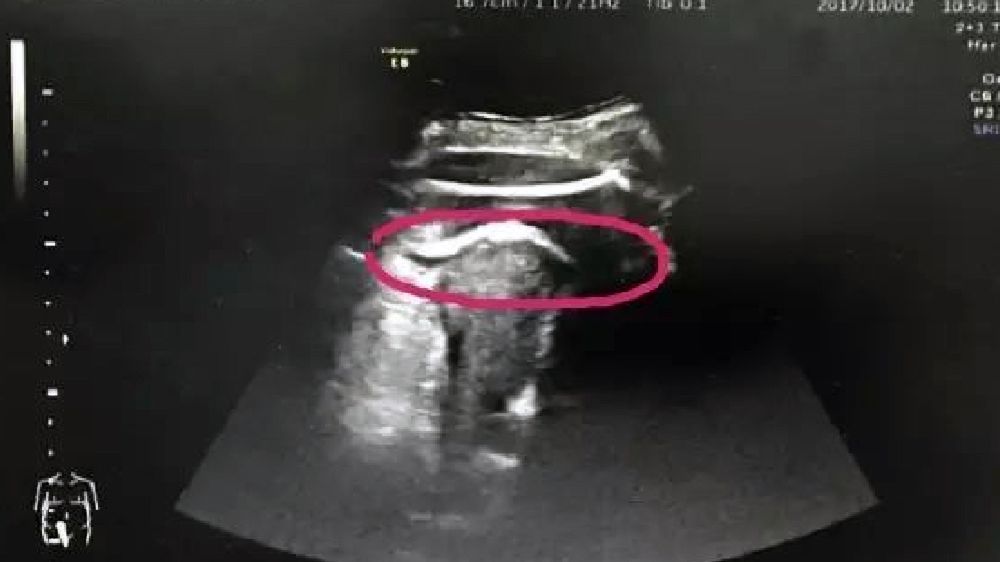

Szpital położniczy w Chinach opisał rzadki przypadek, gdy gwałtowny ruch dziecka w łonie matki dziecka zranił kobietę i wymusił przyśpieszony poród przez cesarskie cięcie.

Gdyby nie oficjalne zdjęcia i opis zabiegu przedstawione przez lekarzy szpitala uniwersyteckiego w Shenzhen, trudno byłoby uwierzyć w taką historię. Kopniak dziecka w brzuchu matki miał okazać się tak silny, że "naruszona została ściana macicy". Do dziś medycyna zna jedynie 26 podobnych przypadków.

Nienarodzona córka pani Zhang kopnęła mamę tak mocno, że przebiła nogą ściankę macicy w miejscu, gdzie kobieta miała bliznę po wcześniej przeprowadzonej operacji. Dziewczynka przyszła na świat w 35 tygodniu ciąży. Oboje z mamą czują się dobrze - czytamy.

Szpital na profilu serwisu społecznościowego QQ opisał przypadek przedwczesnego porodu. 2 października kobieta w pierwszej ciąży trafiła po trwających 5 godzin bólach podbrzusza trafiła na oddział szpitala. Była przekonana, że ma problemy gastryczne. Po zrobieniu USG lekarze szybko odkryli prawdziwe źródło bólu i nakazali operację.

*W 2016 roku pani Zhang przeszła zabieg usunięcia włókniaka macicy. *Sześć miesięcy po operacji zaszła w ciążę. Noga dziecka przebiła ściankę macicy w miejscu, w którym chirurdzy wcześniej operowali. Rozdarcie macicy, według chińskich lekarzy, miało 7 cm długości. Rozdarty został też worek owodniowy. Operujący ciężarną chirurg zaznaczył, że pacjentki po operacjach jak usunięcie mięśniaka powinny czekać z zachodzeniem w ciążę przynajmniej dwa lata.